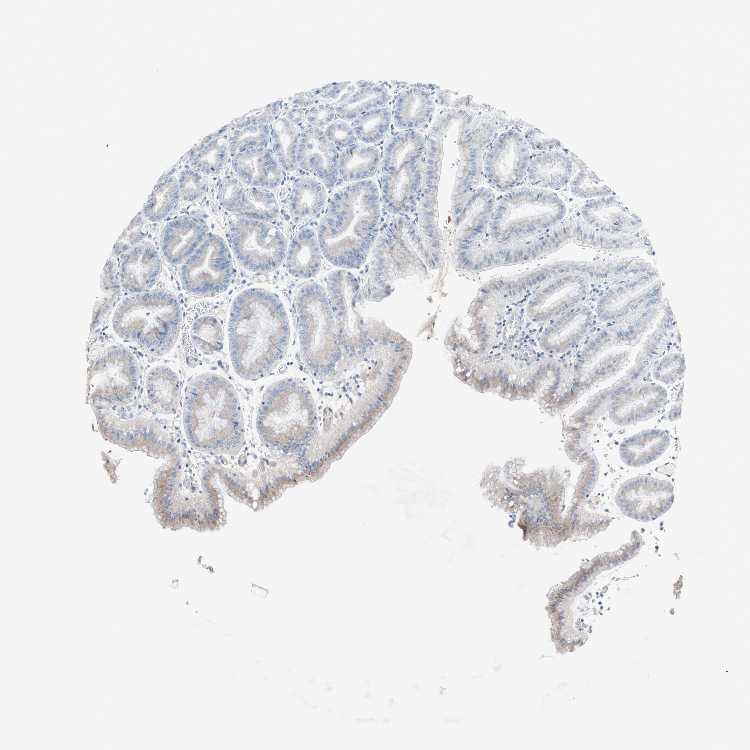

STOMACH 1 - Antibody stainingi

Antibody staining in the annotated cell types in the current human tissue is reported as not detected, low, medium, or high, based on conventional immunohistochemistry profiling in selected tissues. This score is based on the combination of the staining intensity and fraction of stained cells.

Each image is clickable and will lead to virtual microscopy that enables deeper exploration of all samples and also displays staining intensity scores, fraction scores and subcellular localization as well as patient and tissue information for each sample.

Antibody HPA009065

Glandular cells Medium